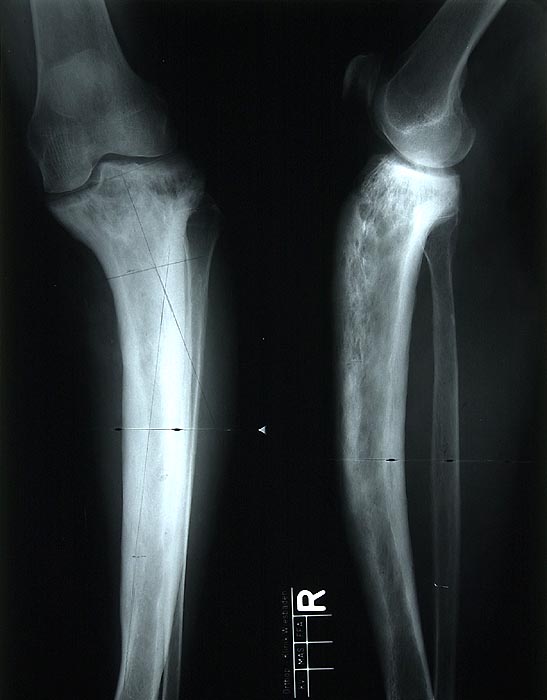

Oft wird die Diagnose als Zufallsbefund in einem Röntgenbild (> 5037) gestellt. Das Röntgenbild zeigt eine erhöhte Knochendichte, eine Verdickung der Corticalis, eine Knochendeformität und eventuell Mikrofrakturen. Die alkalische Phosphatase im Serum ist erhöht, während Kalzium und Phosphatspiegel im Normbereich liegen. Im Urin und im Serum lassen sich erhöhte Hydroxyprolinspiegel nachweisen (Kollagenabbau). Eine Knochenszintigraphie kann als Screeninguntersuchung zur Lokalisierung von Paget Herden verwendet werden.